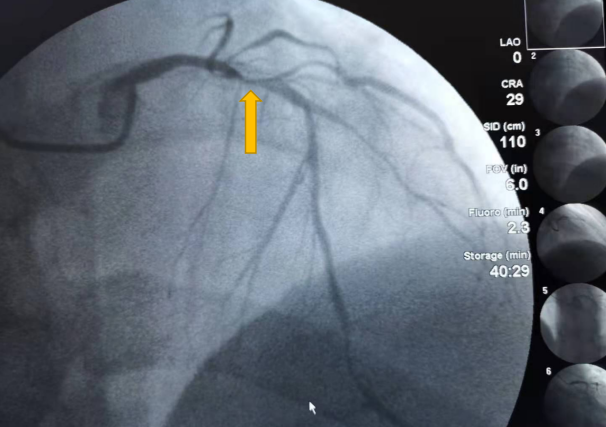

8月6日,行冠脉造影检查结果显示患者左前降支近段血管堵塞95%,为支架内再狭窄,随时都有并发心肌梗塞等严重后果。

术前1

术前2

术前3

经过充分准备后,为患者进行了冠脉内血管超声检查(IVUS),获得前降支近段真实管腔直径2.8mm、实际测得有效官腔直径小于1mm,狭窄处明显见钙化,钙化环约330°、病变长度达23m等信息。